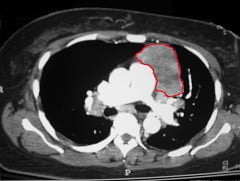

Новообразованиями вышеуказанного анатомического пространства являются как истинные опухоли средостения, так и отличные по локализации, протеканию и этиологии кисты и опухолевые недуги. Каждое новообразование этого органа формируется из тканей разного происхождения, объединяясь лишь анатомическими границами.

Лимфаденопатия (увеличение лимфатических узлов) средостения наблюдается, как правило, при лимфомах, метастазах карциномы и некоторых других неопухолевых заболеваниях (туберкулез, саркоидоз и проч.).